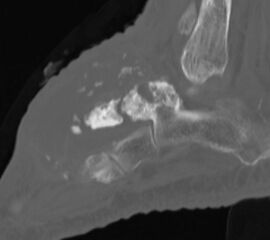

Axiale CT-Aufnahmen eines Osteoidosteoms im Bereich des Calcaneus mit typischer Nidusbildung und perifokaler Sklerose (links). Bildgesteuerte Thermofrequenzablation der Läsion (rechts).

Die Computertomographie (CT) wird seltener als die MRT herangezogen um eine spezi­fischen Artdiagnose zu finden, liefert aber wertvolle Informationen zur Kortikalis­beschaffen­heit (Kontinuität, Stärke, enostale Arrosion) unterschiedlichster Knochenläsionen. Insbe­sondere die enostale Kortikalisarrosion, wie sie häufig bei chondrogenen Tumoren anzu­treffen ist, kann konkrete Hinweise liefern, die in Zusammenschau mit histologischen Befunden zu einer definitiven Diagnose führen (siehe Spezifische Entitäten: Enchondrom vs. atypischer chondrogener Tumor/Chondrosarkom). Die Computertomographie ist außerdem hilfreich in der Abgrenzung komplexer anatomischer Strukturen (z.B. 3D-Rekonstruktion) und sehr kleiner Knochenläsionen. Bei der Diagnose des Osteoidosteoms bleibt die CT Mittel der Wahl um die charakteristischen Veränderungen in der bildgebenden Diagnostik exakt darzustellen (Abb. 6). Die Gewebedichte von weichteiligen Tumoren, insbesondere von intra- und extraossären Lipomen, kann im Vergleich zum subkutanen Fettgewebe mithilfe der Houndsfield-Skala beurteilt werden.